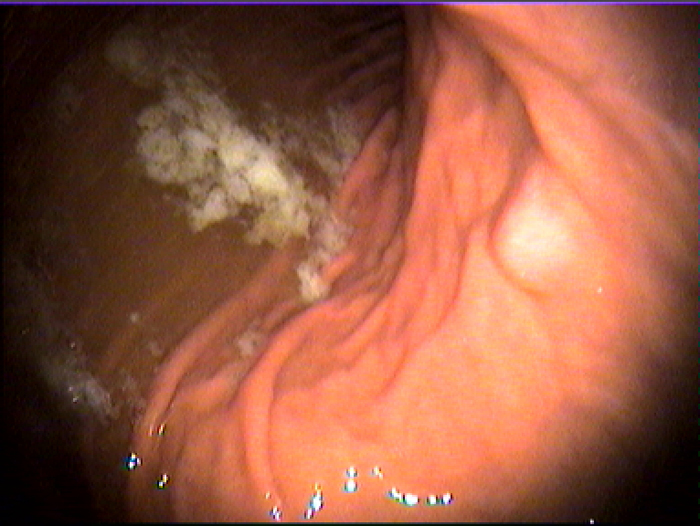

胃肠科

萎缩性胃炎常见的表现有餐后饱胀,食欲减退,消化不良,上腹部痛,恶心,呕吐等症状。萎缩性胃炎的潜在危害有哪些?这是很多患者朋友关心的问题。福州台江医院医师做如下解答。

萎缩性胃炎的症状有哪些?

萎缩性胃炎的症状有哪些,并不是每一位患者都知道。一些患者会把萎缩性胃炎误认为是其他类型的胃部疾病。一般而言,萎缩性胃炎会有以下症状。